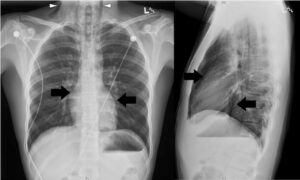

Derrame pleural é o acúmulo anormal de líquido no espaço pleural. Os principais sinais na radiografia são:...